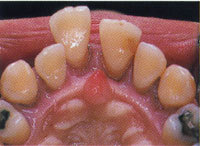

▼術前

▼SPR前

ブラッシングによるプラークコントロールで歯ぐきの腫れが徐々に改善してきました。

歯ぐきが赤く腫れぶよぶよし、深い歯周ポケットには膿がたまっています。病気の進行により、歯並びも乱れています。